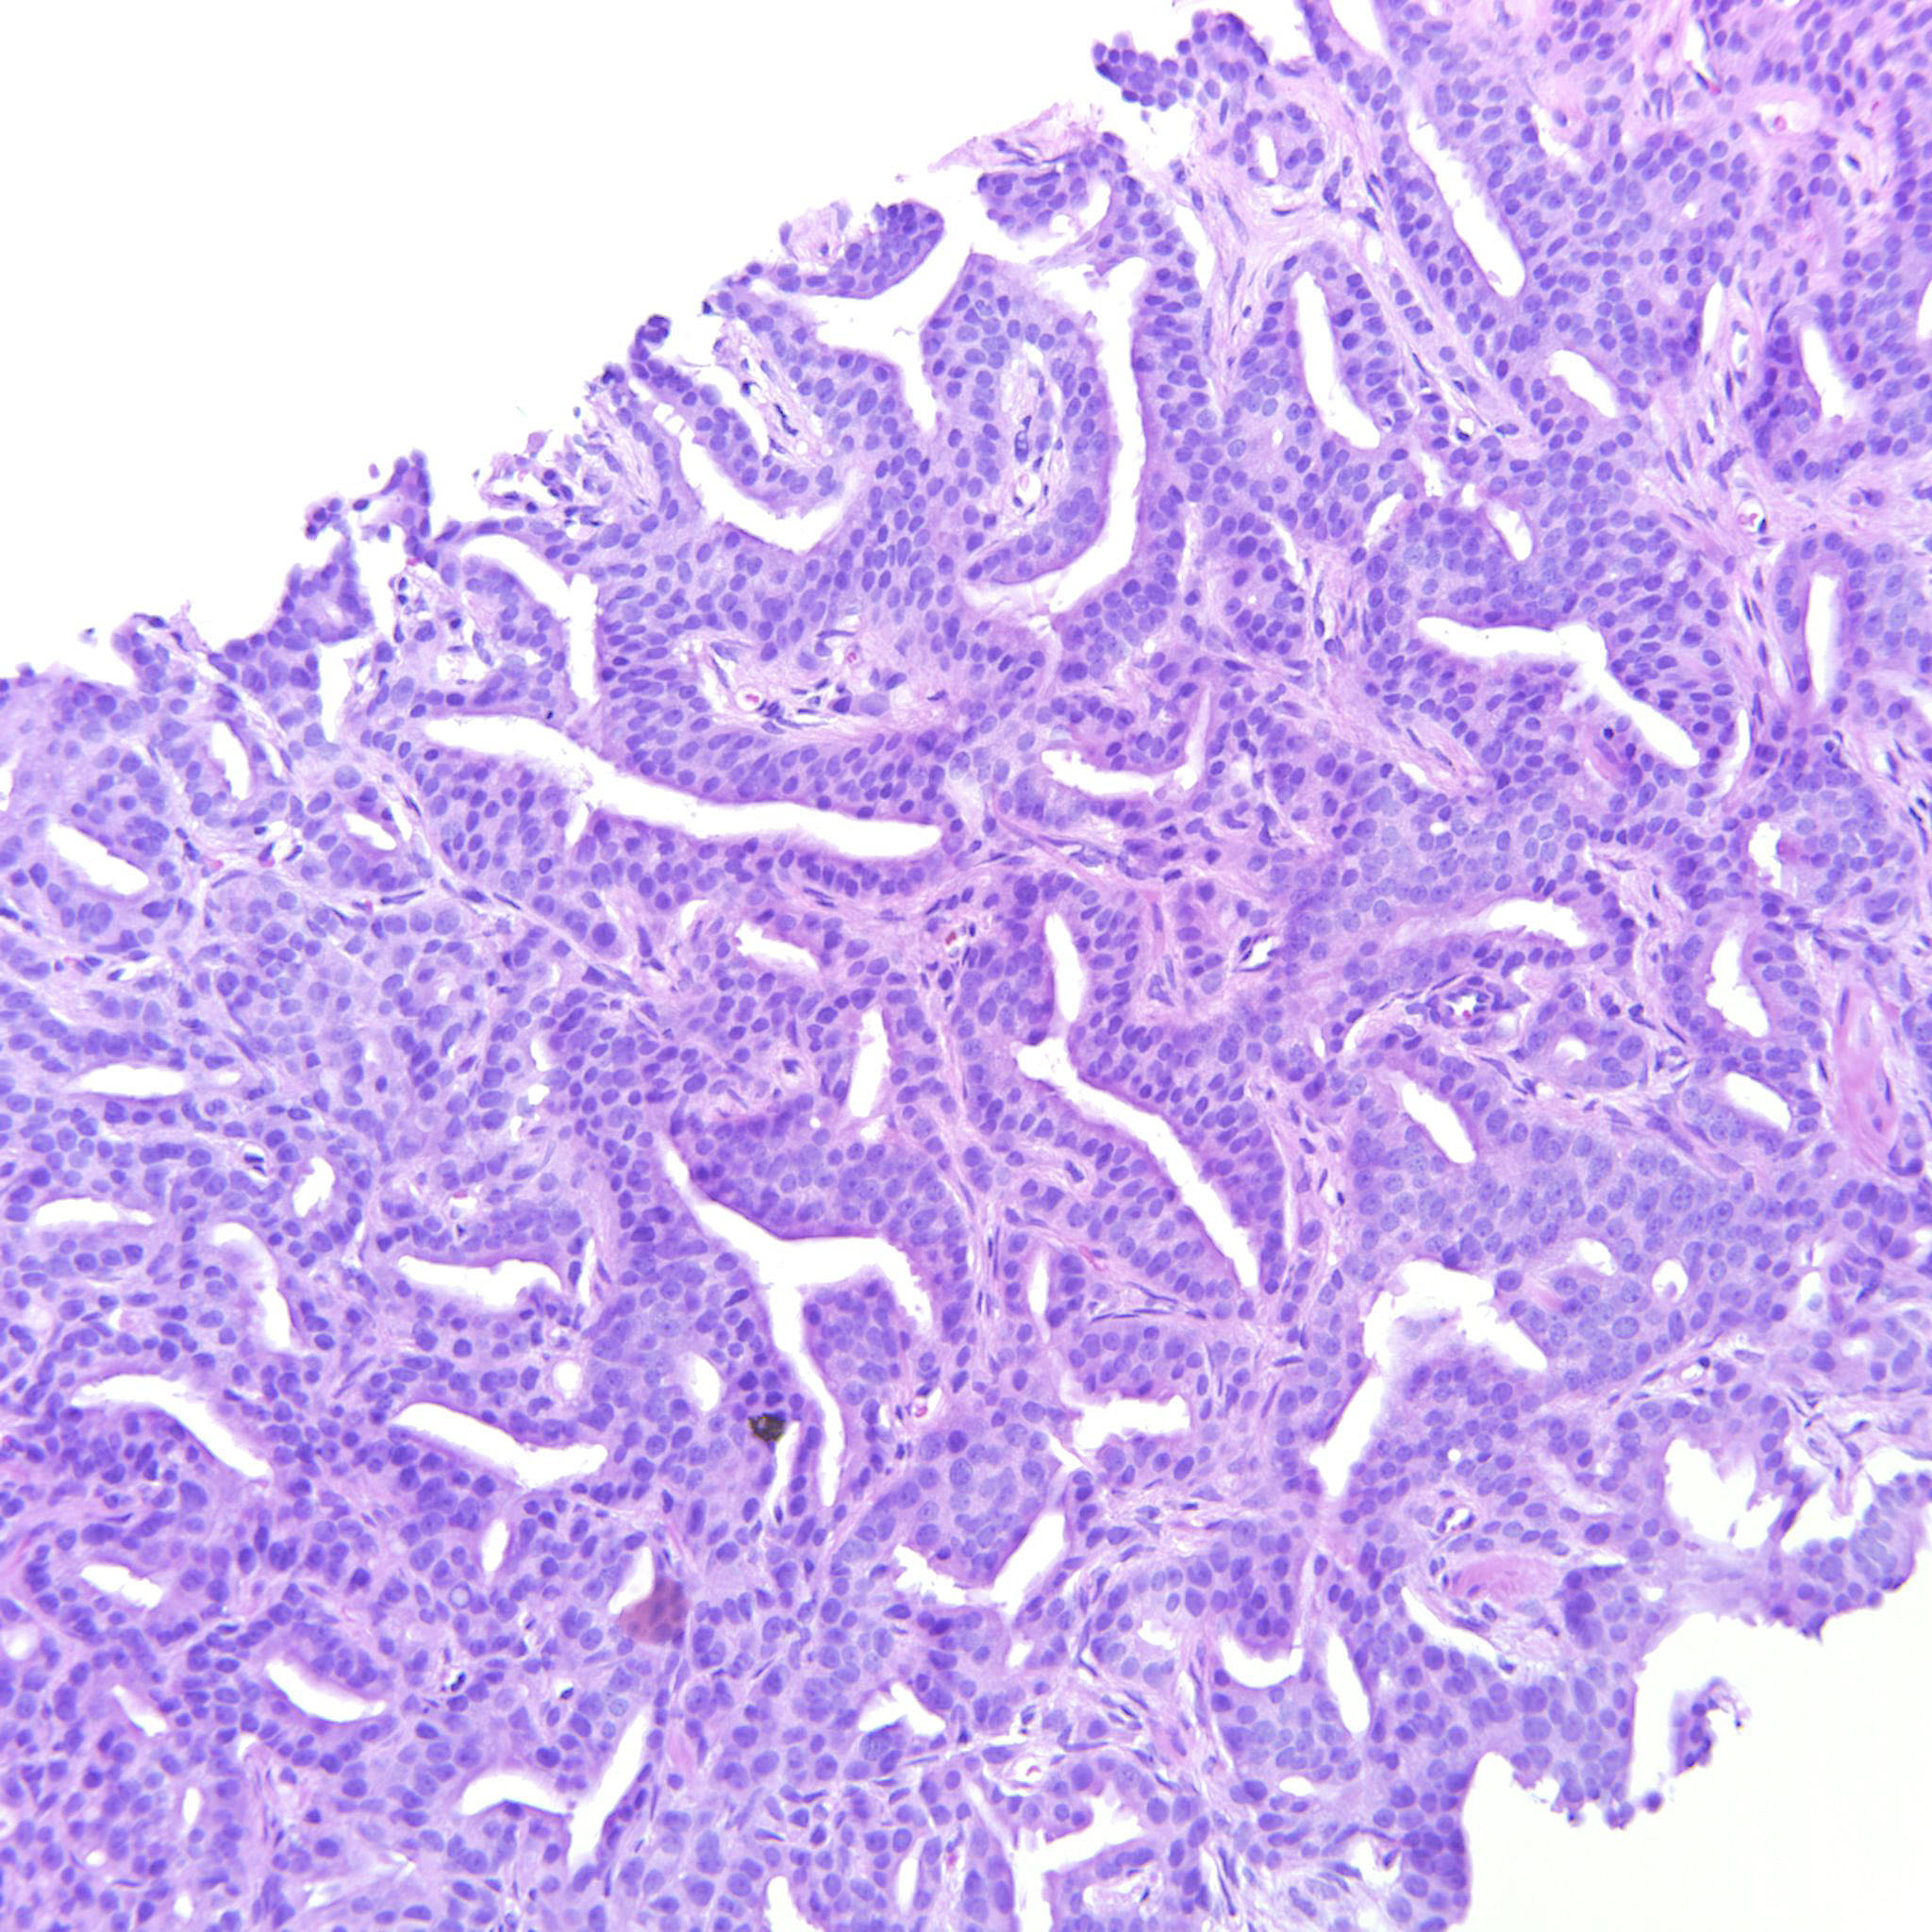

Prostate cancer grading

Case ID: 306